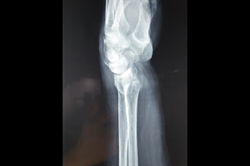

Lower Radius